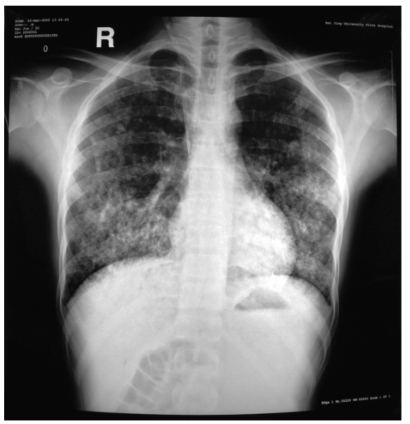

血 WBC 8.27×109/L,PLT 238×109/L,Hb 81.0g/L。ESR 26mm/h。尿 RBC满视野,为变形红细胞,尿蛋白定量 4.67g/d。血 SCr 634.0μmol/L,BUN 26.3mmol/L,ALB 24.3g/L,肝功能正常。RF阴性,CRP阳性,ANCA阴性,ANA、抗dsDNA、ENA阴性,抗GBM抗体阳性(百分结合率98%)。动脉血气分析:pH 7.352,PO269mmHg,PCO238mmHg,SaO293%。 胸片:两肺满布粟粒状模糊影,以两肺中下野为著,部分融合成团片状,肺野透过度差(图1)。

图1胸部正位片

双肺粟粒状模糊影,以两肺中下野为著